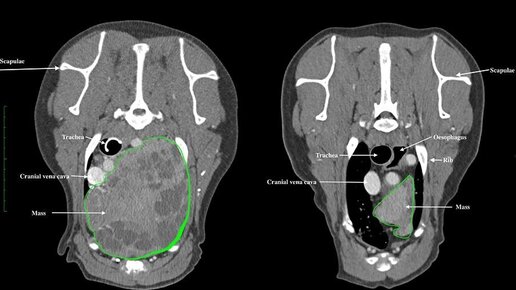

Специалисты клиники школы ветеринарных исследований Эдинбургского университета рассказали об успешной терапии рака и остеоартрита у 11-летней собаки с помощью лучевой терапии. Для лечения применяли линейный ускоритель, используемый для лучевой терапии онкологических патологий у людей. Пациент - собака с диагнозом тимома (рак вилочковой железы, локализованный в грудной клетке) и размером опухоли более 15 см (по КТ - исследованию). Патологическое образование давило на сердце, легкие, трахею, пищевод...